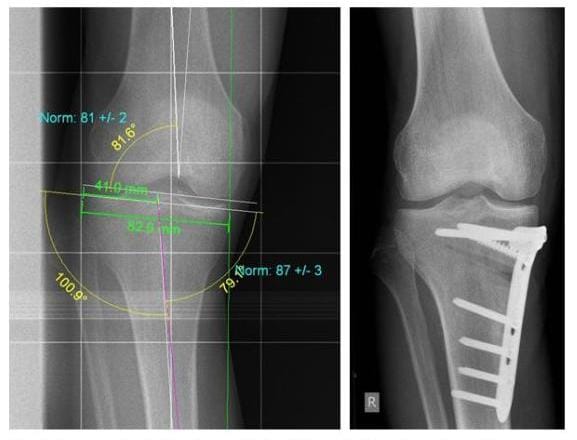

Röntgenbild nach Analyse der Fehlstellung erfolgte die Korrektur eines O-Beines durch eine medial aufklappende Umstellungsosteotomie

Nach Analyse der Fehlstellung (links) erfolgte die Korrektur eines O-Beines durch eine medial aufklappende Umstellungsosteotomie (rechts). (Bilder: Orthopädie)